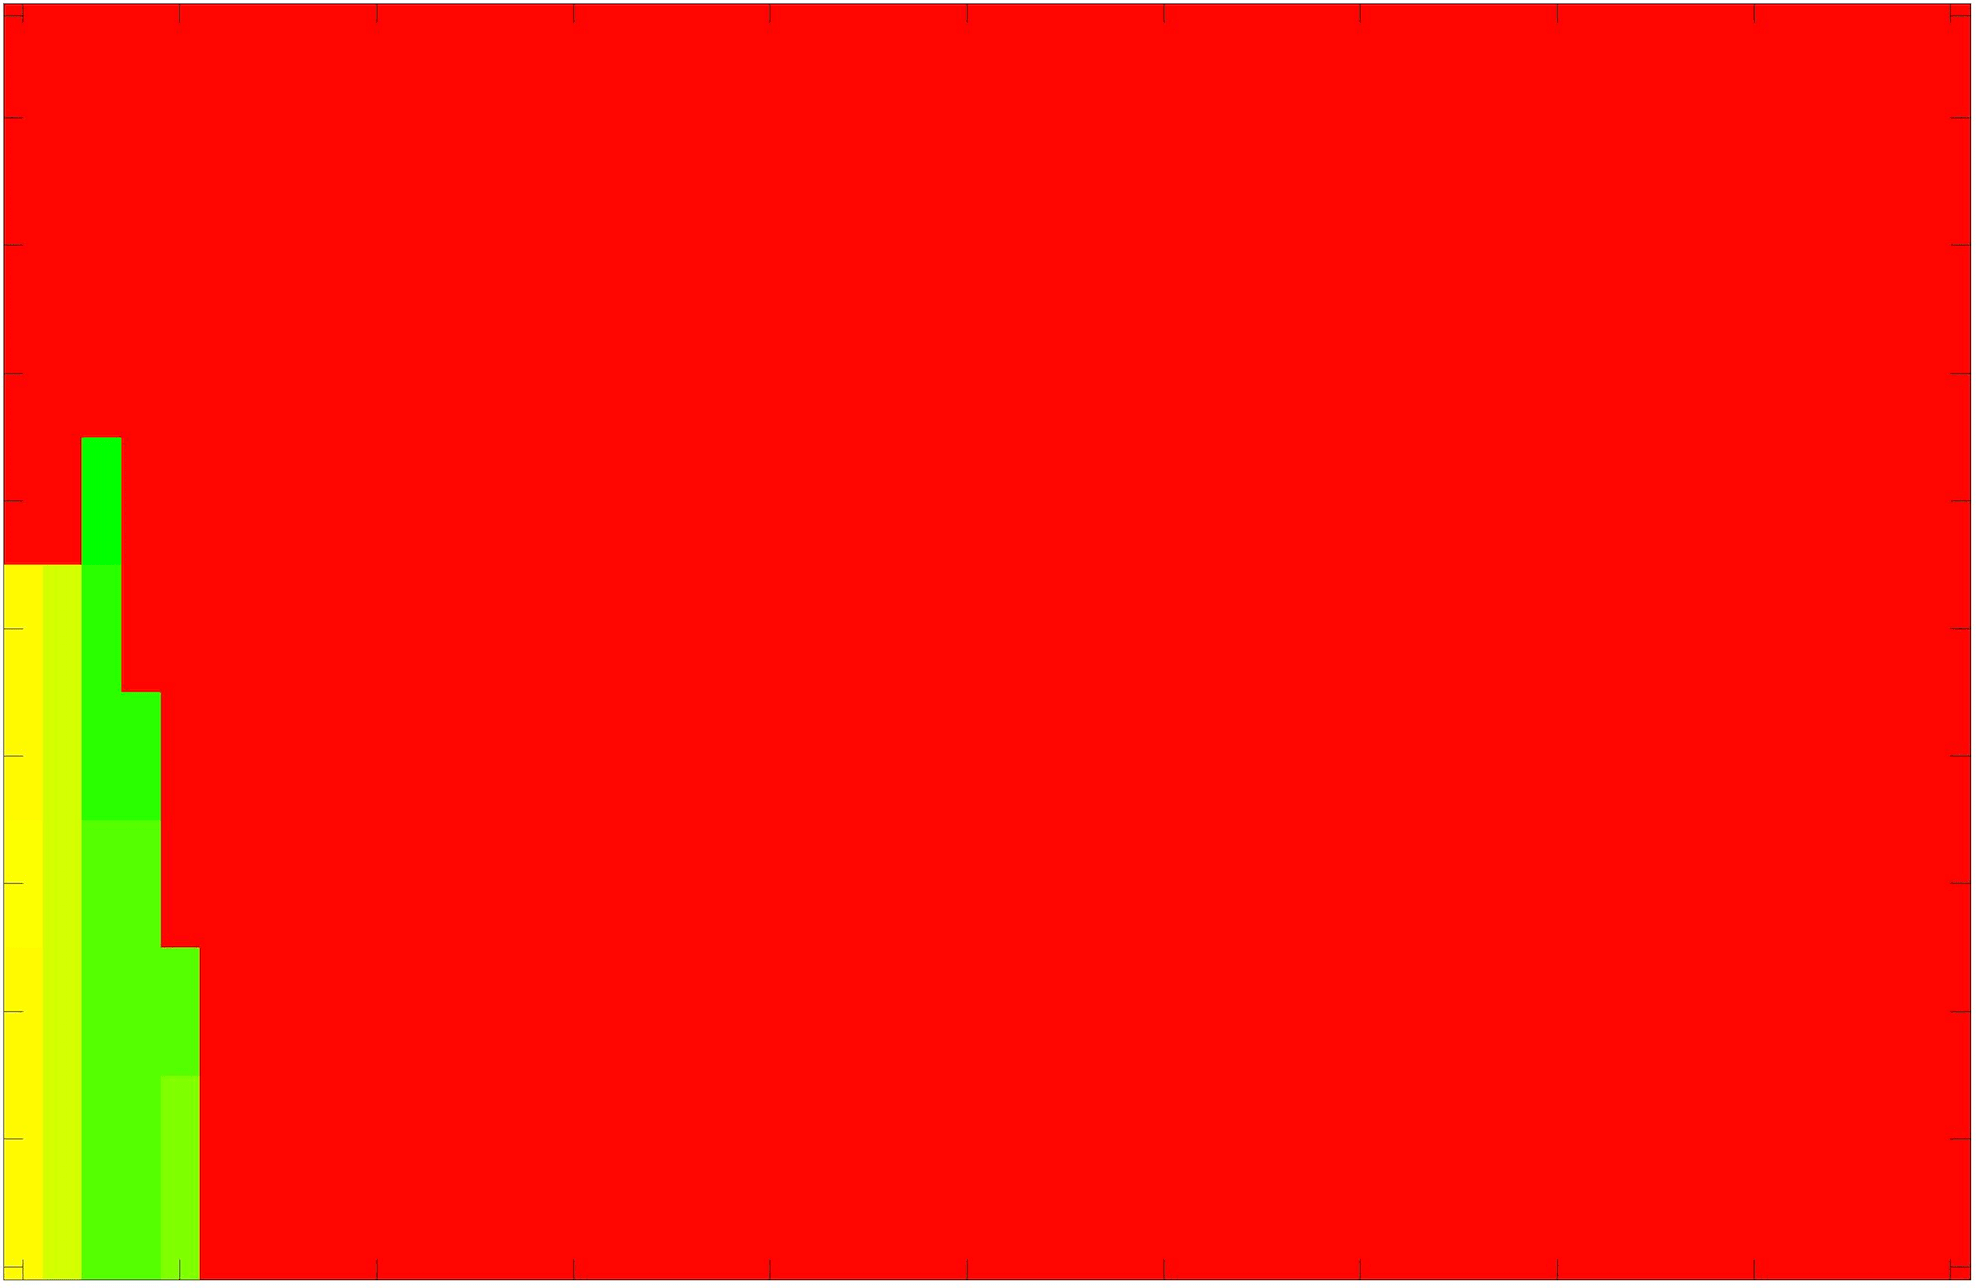

where refers to the number of points in the enclosed region. This takes values in the range , with higher TC values indicating a more accurate segmentation. In the following we will represent accuracy visually from red () to green (), with the intermediate scaling of colours used shown in Fig. 8. This will be particularly relevant in §7.2.

The TC values for the parameter sets are presented as heatmaps in Figs. 11–13. A heatmap is a convenient way to display accuracy results for hundreds of tests concisely. In Fig. 9 we give an example heatmap with the same axes used for those in Figs. 11–13. For each of the combinations of parameter values we give the TC value of the segmentation result and represent it by the appropriate colour. The corresponding colour scale is shown in Fig. 8. Qualitatively, the more green areas of the heatmap the more accurate the model is for a wider set of parameters. Example results for Test Image 5 when varying (with ) for the proposed model are given in Fig. 10. Here it can be seen what each accuracy result corresponds to visually.

Note. The axes have been removed from the heatmaps in Figs. 11–13 for presentational clarity. However, to be explicit, the axes used in all heatmaps are the same as those in Fig. 9.